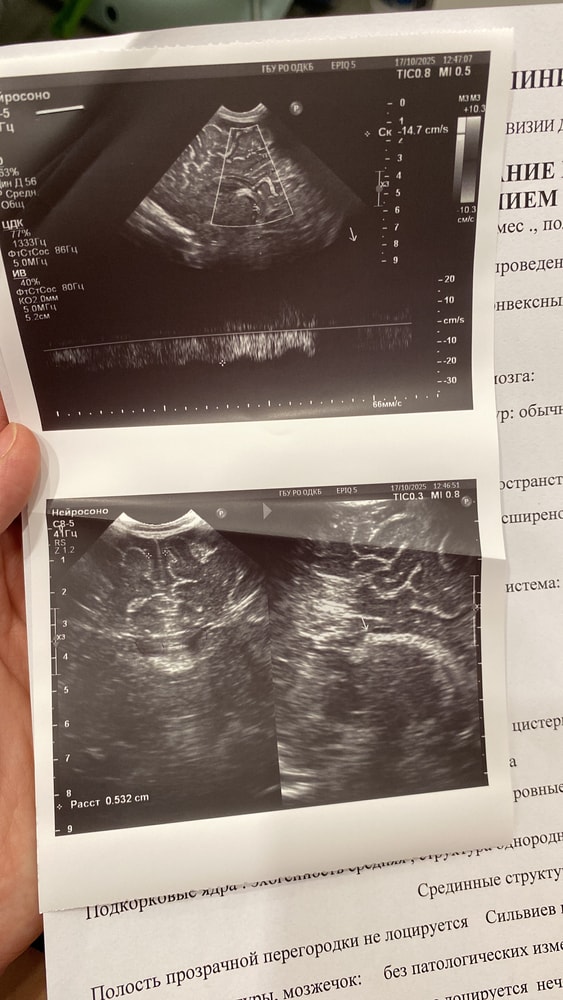

Добрый день. Прошу дочитать до конца и помочь, если у кого была такая ситуация. Мама впервые, ребёнку 3 месяца. Прошли нейросонограмму в детской больнице по месту жительства и поехали на консультацию к неврологу в детскую областную больницу нашего города, так как в нашей поликлинике невролога не было. Причина посещения- поворачивает голову постоянно вправо, как бы не клала, не заинтересовывала игрушками, даже ночью ему постоянно голову поворачивала в другую сторону, все бестолку. И плюс начали закрадываться опасения, что плохо держит голову. По НСГ небольшая псевдокиста, увеличены боковые желудочки. Я уже почитала, что так у многих детей и к году обычно рассасывается само. В общем попали к неврологу, при осмотре было сказано, что плечи в тонусе, синдром короткой шеи, левые мышцы слабее правых, и бонусом ноги в тонусе. Поставили его на ноги, опора есть, но пальцы не разжимает на ногах. А когда тянули за ручки, он не подтягивался вслед, голова так и оставалась висеть. Голову держит плохо, 10 минут не выдерживает лежать на животе, потом роняет голову и начинает заливаться плачем. В общем отправили нас на повторную НСГ строго в областной, ибо невролог доверяет только их результатам, наша НСГ ей «не подошла», и плюс сделать глобальную электромиографию только в определенном центре и только у определенного врача. Ну, делать нечего, сделали, ниже прикреплю фото. В целом невролог не плохой, но вот уж очень смущают меня назначения, которые она выписала. Может кто был в похожей ситуации, какой курс лечения все таки выбрать? Однозначно пойду за 3 мнением к другому неврологу, не хочется 3 месячного ребёнка пичкать препаратами. Я вообще думала только массажем да электрофорезом обойдется